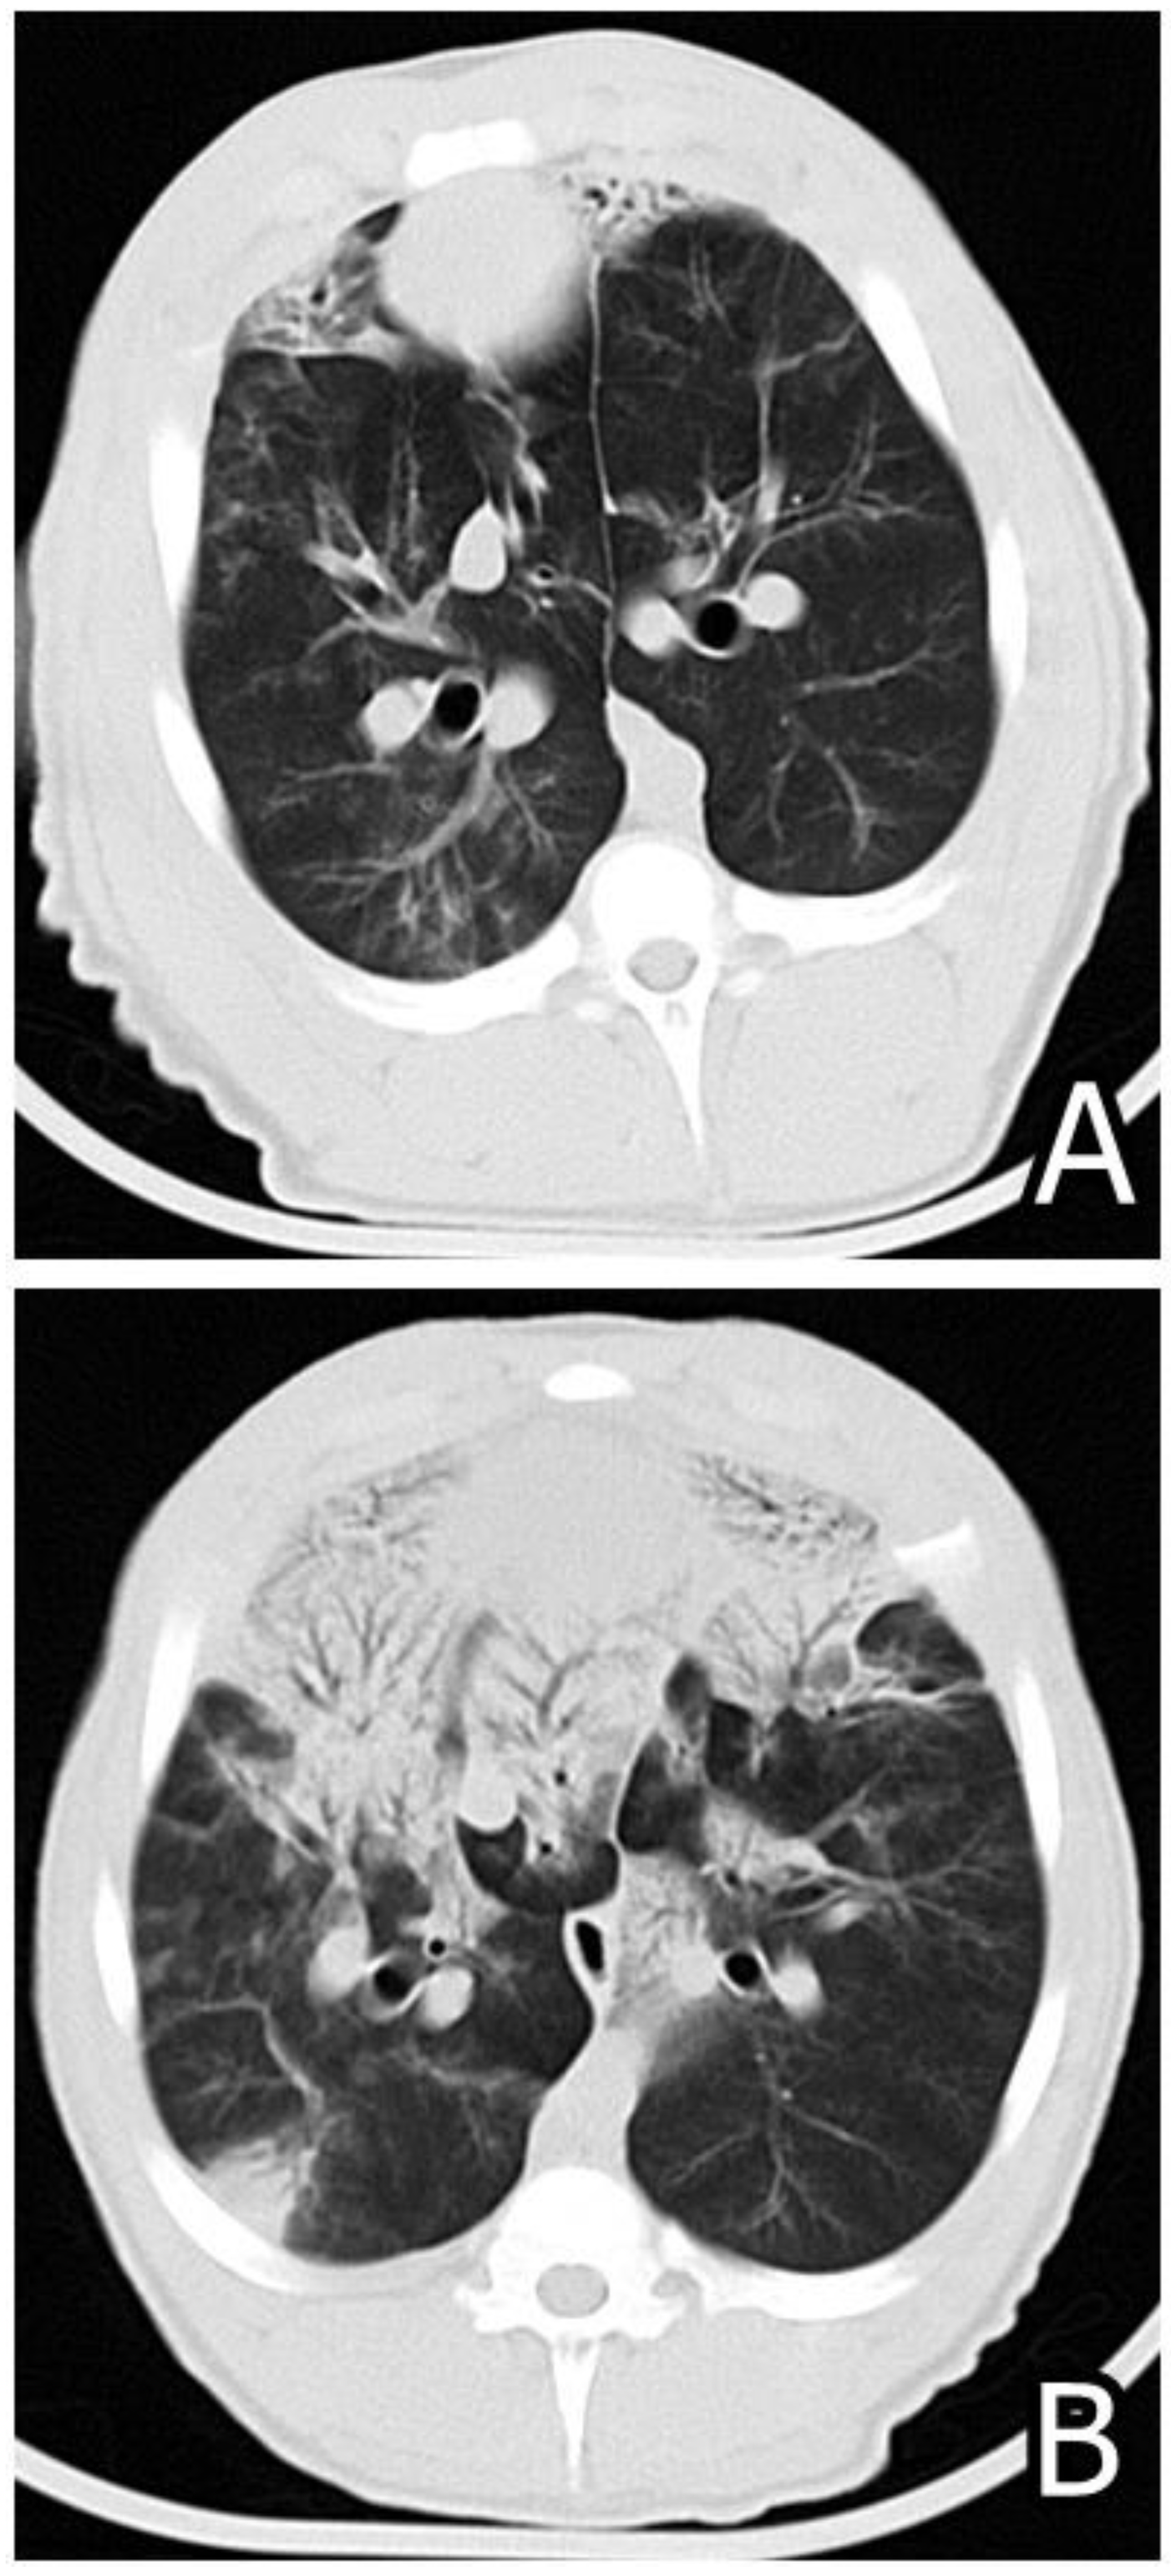

- Pósa, R.; Donkó, T.; Bogner, P.; Kovács, M.; Repa, I.; Magyar, T. Interaction of Bordetella bronchiseptica, Pasteurella multocida and fumonisin B1 in the porcine respiratory tract followed up by computed tomography. Can. J. Vet. Res. 2011, 75, 176–183. [Google Scholar] [PubMed]

- Pósa, R.; Magyar, T.; Stoev, S.D.; Glávits, R.; Donkó, T.; Repa, I.; Kovács, M. Use of Computed Tomography and Histopathologic Review for Lung Lesions Produced by the Interaction between Mycoplasma hyopneumoniae and Fumonisin Mycotoxins in Pigs. Vet. Pathol. 2013, 50, 971–979. [Google Scholar] [CrossRef] [PubMed]

- Pósa, R.; Stoev, S.D.; Kovács, M.; Donkó, T.; Repa, I.; Magyar, T. A comparative pathological finding in pigs exposed to fumonisin B1 and/or Mycoplasma hyopneumoniae. Toxicol. Ind. Health 2016, 32, 998–1012. [Google Scholar] [CrossRef] [PubMed]